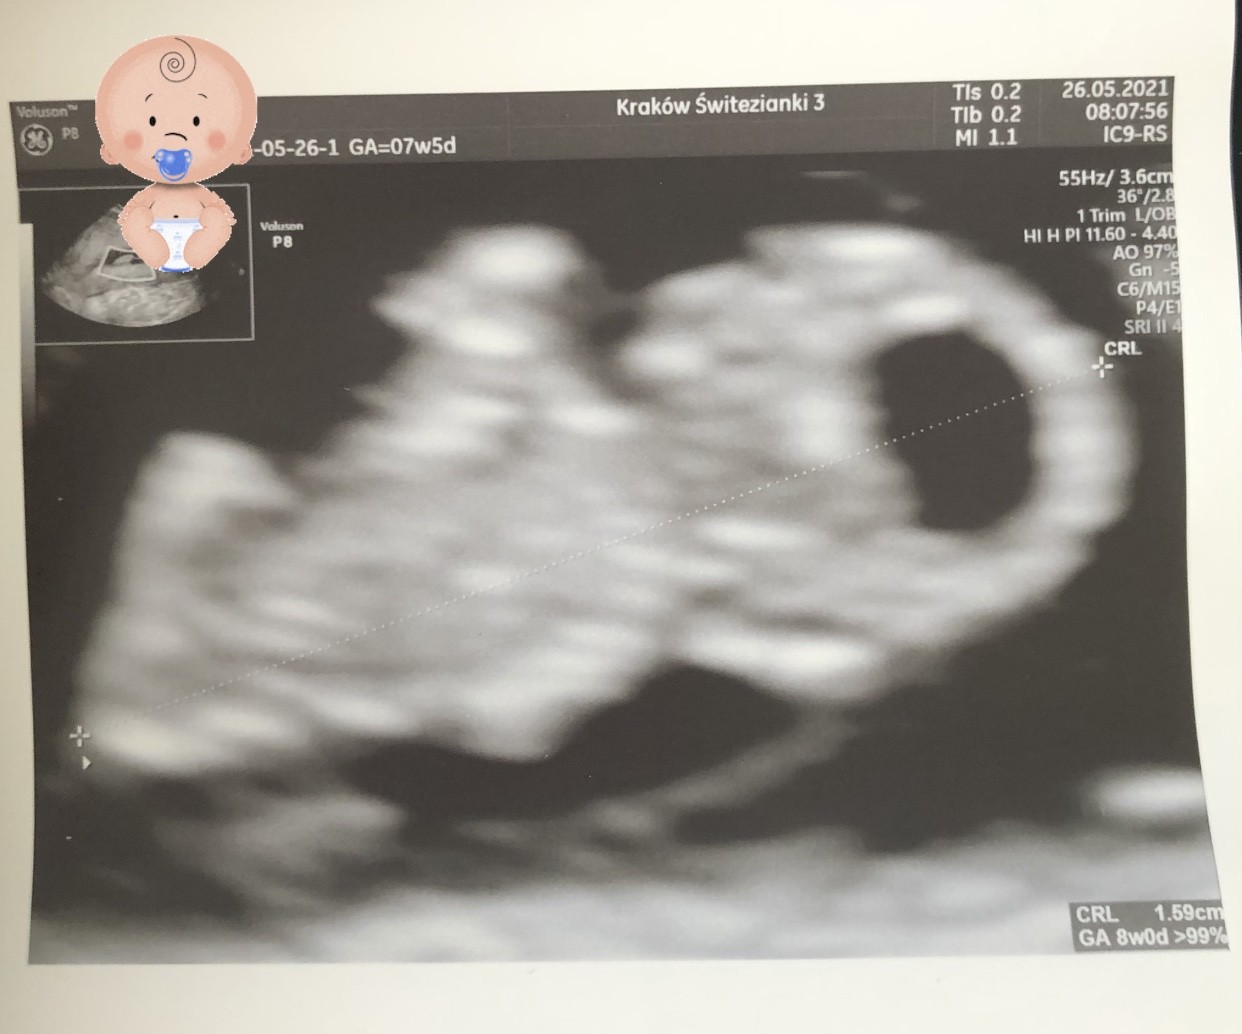

Hej dziewczyny 🙂 ja co prawda miałam wizytę rano, ale dopiero teraz mam czas napisać. Wszystko jest dobrze, serduszko ładnie bije, dzidziuch większy o 2 dni. Następna wizyta dopiero 30.06 🙊

Załączniki

• A1FFD6C2-EDB8-46AF-AC21-2333CFB93578.jpeg

A1FFD6C2-EDB8-46AF-AC21-2333CFB93578.jpeg

163,4 KB · Wyświetleń: 147